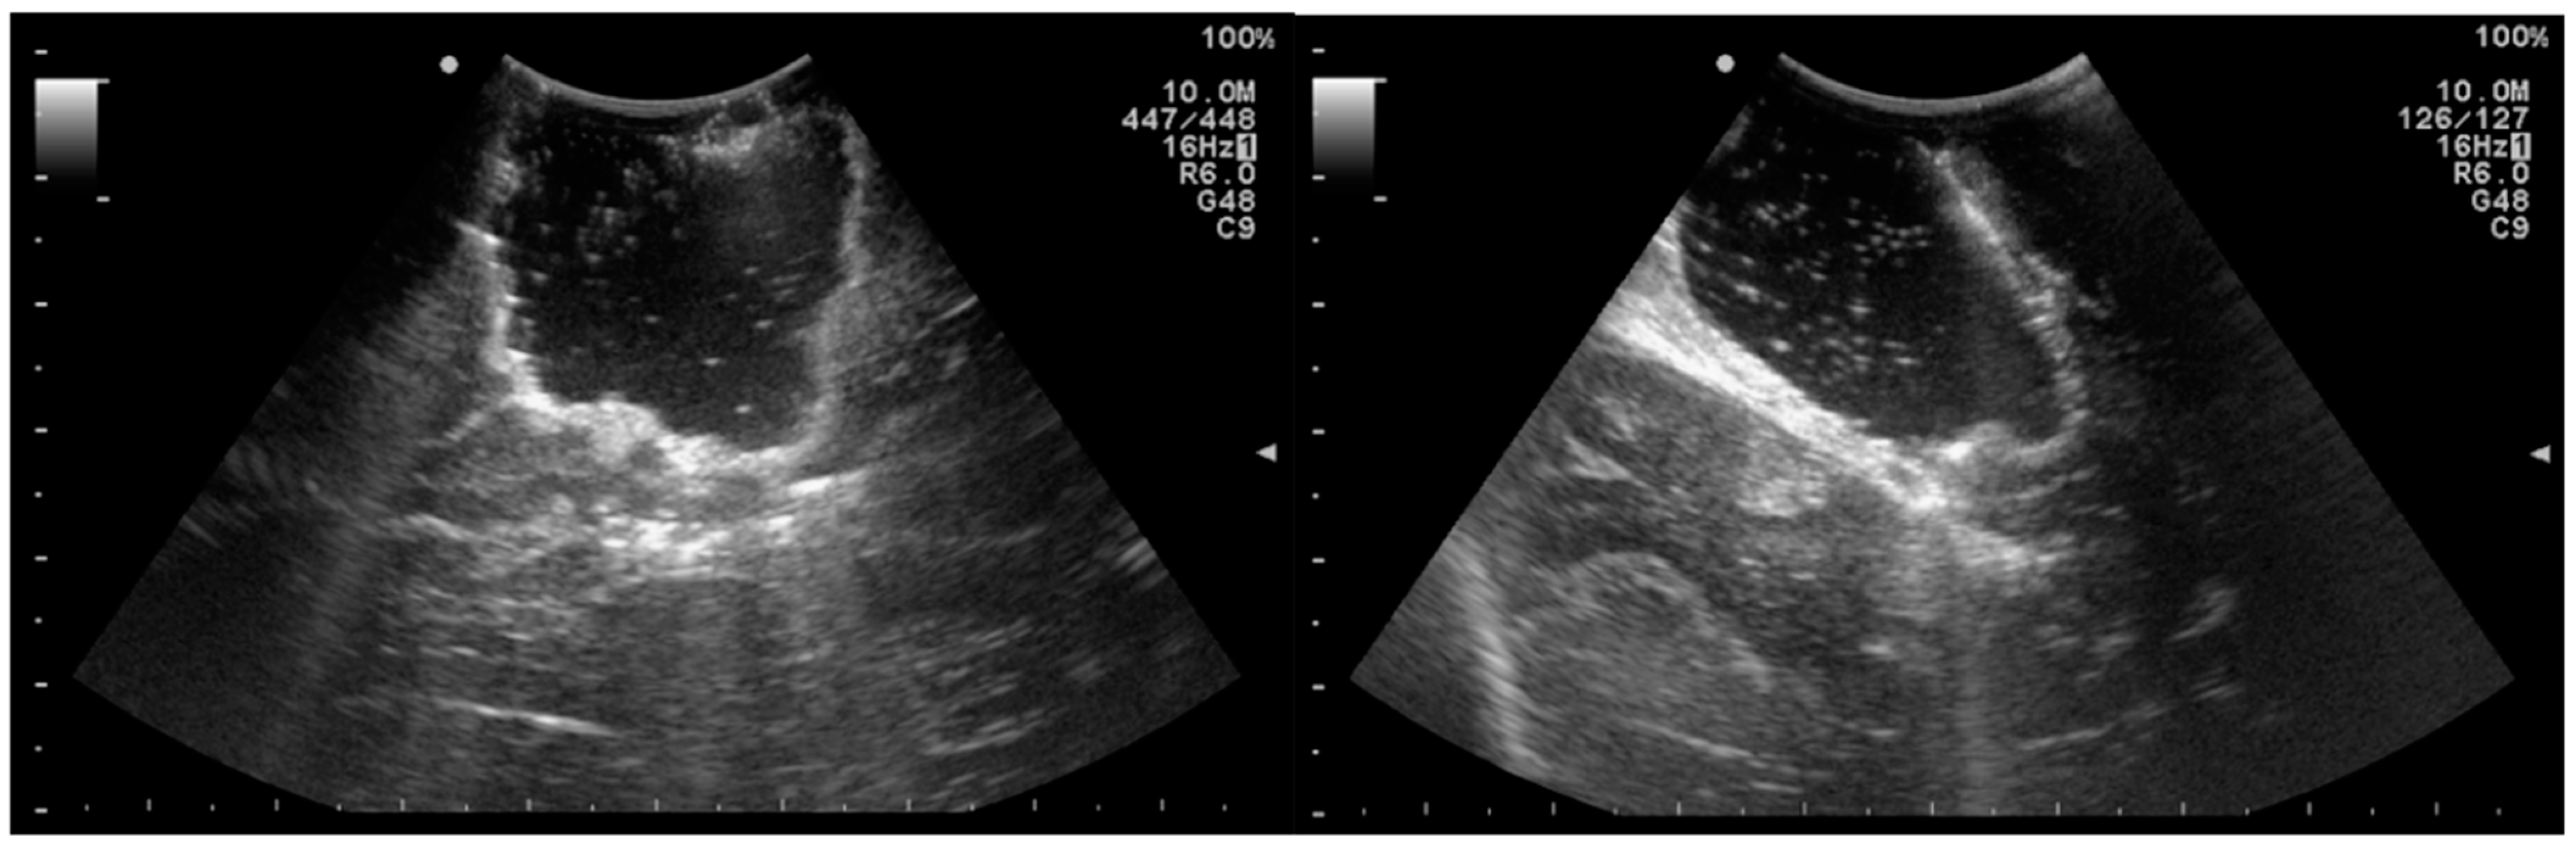

- Prada, F.; Del Bene, M.; Fornaro, R.; Vetrano, I.G.; Martegani, A.; Aiani, L.; Sconfienza, L.M.; Mauri, G.; Solbiati, L.; Pollo, B.; et al. Identification of residual tumor with intraoperative contrast-enhanced ultrasound during glioblastoma resection. Neurosurg. Focus 2016, 40, E7. [Google Scholar] [CrossRef] [PubMed] [Green Version]

- Moiraghi, A.; Prada, F.; Delaidelli, A.; Guatta, R.; May, A.; Bartoli, A.; Saini, M.; Perin, A.; Wälchli, T.; Momjian, S.; et al. Navigated Intraoperative 2-Dimensional Ultrasound in High-Grade Glioma Surgery: Impact on Extent of Resection and Patient Outcome. Oper. Neurosurg. 2019, 18, 363–373. [Google Scholar] [CrossRef] [PubMed]

| Prada et al., 2016 [72] | Prospective | 10 patients with GBM | CEUS was extremely specific in identifying residual tumor |

| Moiraghi et al.,2020 [73] | Retrospective | 60 patients with supratentorial gliomas | N-ioUS improved EOR and neurological outcomes |